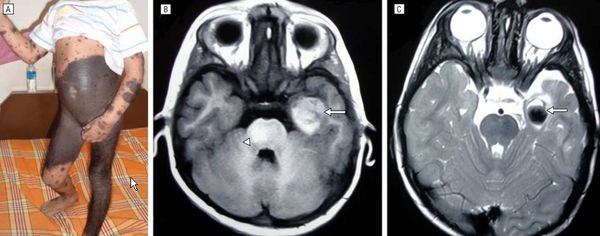

Представлен случай редко встречающегося врожденного гигантского меланоцитарного волосяного невуса. Данное клиническое наблюдение демонстрирует необходимость оценки степени вероятности паранеопластического характера дерматоза.

Больная Р., 35 лет, находилась на стационарном лечении и обследовании в женском кожном отделении Республиканского кожно-венерологического диспансера с диагнозом «гигантский меланоцитарный невус». Субъективные жалобы на умеренную болезненность в области высыпаний, легкий зуд. По данным анамнеза росла и развивалась соответственно возрасту, наличие туберкулеза и венерических болезней отрицает, другие соматические заболевания, наличие аллергических реакций не отмечает. Больна данным заболеванием с рождения. Беременность и роды у матери протекали без патологии. Размеры высыпаний увеличивались по мере роста ребенка. По месту жительства к врачам не обращалась. Обследование проходила в Москве. В связи с появившимися жалобами, нарастанием выраженности клинических проявлений направлена на госпитализацию в ГУ РКВД.

В легких везикулярное дыхание, хрипов нет. Тоны сердца ясные, ритмичные. Артериальное давление — 120/80 мм рт.ст., пульс — 76 ударов в минуту. Живот мягкий, безболезненный при пальпации. Печень у края реберной дуги. Симптом Пастернацкого отрицательный с обеих сторон. Физиологические отправления в норме. Периферические лимфатические узлы не пальпируются. Патологический процесс занимает обширные участки на коже туловища, конечностей, представлен высыпаниями темно-коричневого цвета с бугристой, бородавчатой поверхностью, участками выраженного гипертрихоза, местами определяются трещины кожи. При осмотре выявляются невусы средних размеров, диаметром 1,5 см, в виде разбросанных папул на коже живота (рис. 1—4). Рисунок 1. Высыпания гигантского невуса на коже живота. Рисунок 2. Высыпания гигантского невуса на коже туловища и правого бедра. Рисунок 3. Высыпания гигантского невуса на коже спины. Рисунок 4. Очаги меланоцитарного невуса на коже боковой поверхности туловища и передней поверхности правого бедра. Слившиеся крупные очаги занимают всю поясничную область, боковую правую поверхность туловища и переходят на область правого бедра, где гипертрихоз выражен в большой степени (рис. 5—6). Рисунок 5. Очаги меланоцитарного невуса на коже поясничной области и задней поверхности правого бедра. Рисунок 6. Высыпания гигантского волосяного невуса на коже спины и правого бедра.

При обследовании материала, взятого из очага поражения (цитологическое исследование), специфических изменений не выявлено. Рутинные клинико-лабораторные методы обследования без патологии. В стационаре больной выставлен клинический диагноз «врожденный гигантский волосяной меланоцитарный невус».

При повторной консультации признаков малигнизации и негативной динамики кожного процесса не наблюдалось. Во время курса лечения в стационаре ГУ РКВД наблюдалось уменьшение субъективной симптоматики в виде улучшения самочувствия, стихания болей в области высыпаний, уменьшения зуда.